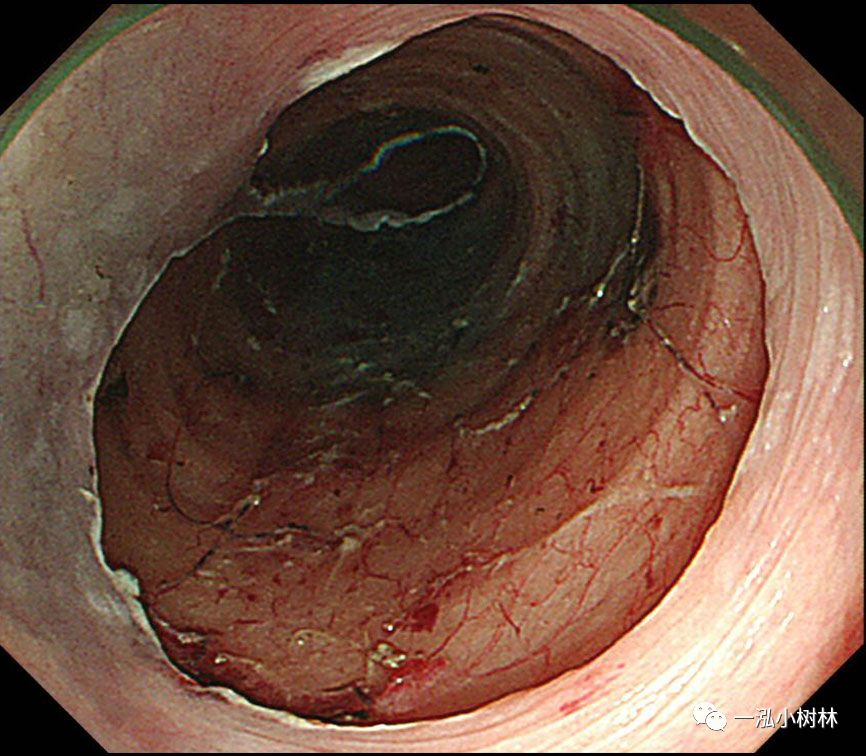

图10 牵引线从嘴中拉出以产生牵引力